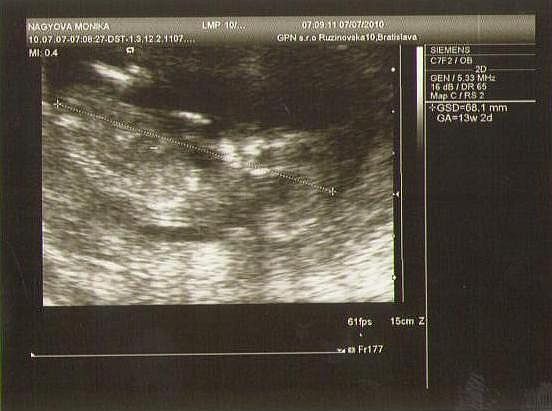

Dnes som bola na tom NT a všetko vyzerá v norme ,ešte to porovnajú s odberom krvi a potom to budem vedieť presne ...drobček rastie ,srdiečko bije ,hýbe sa jedna radosť ,tak sa teším ! 🙂